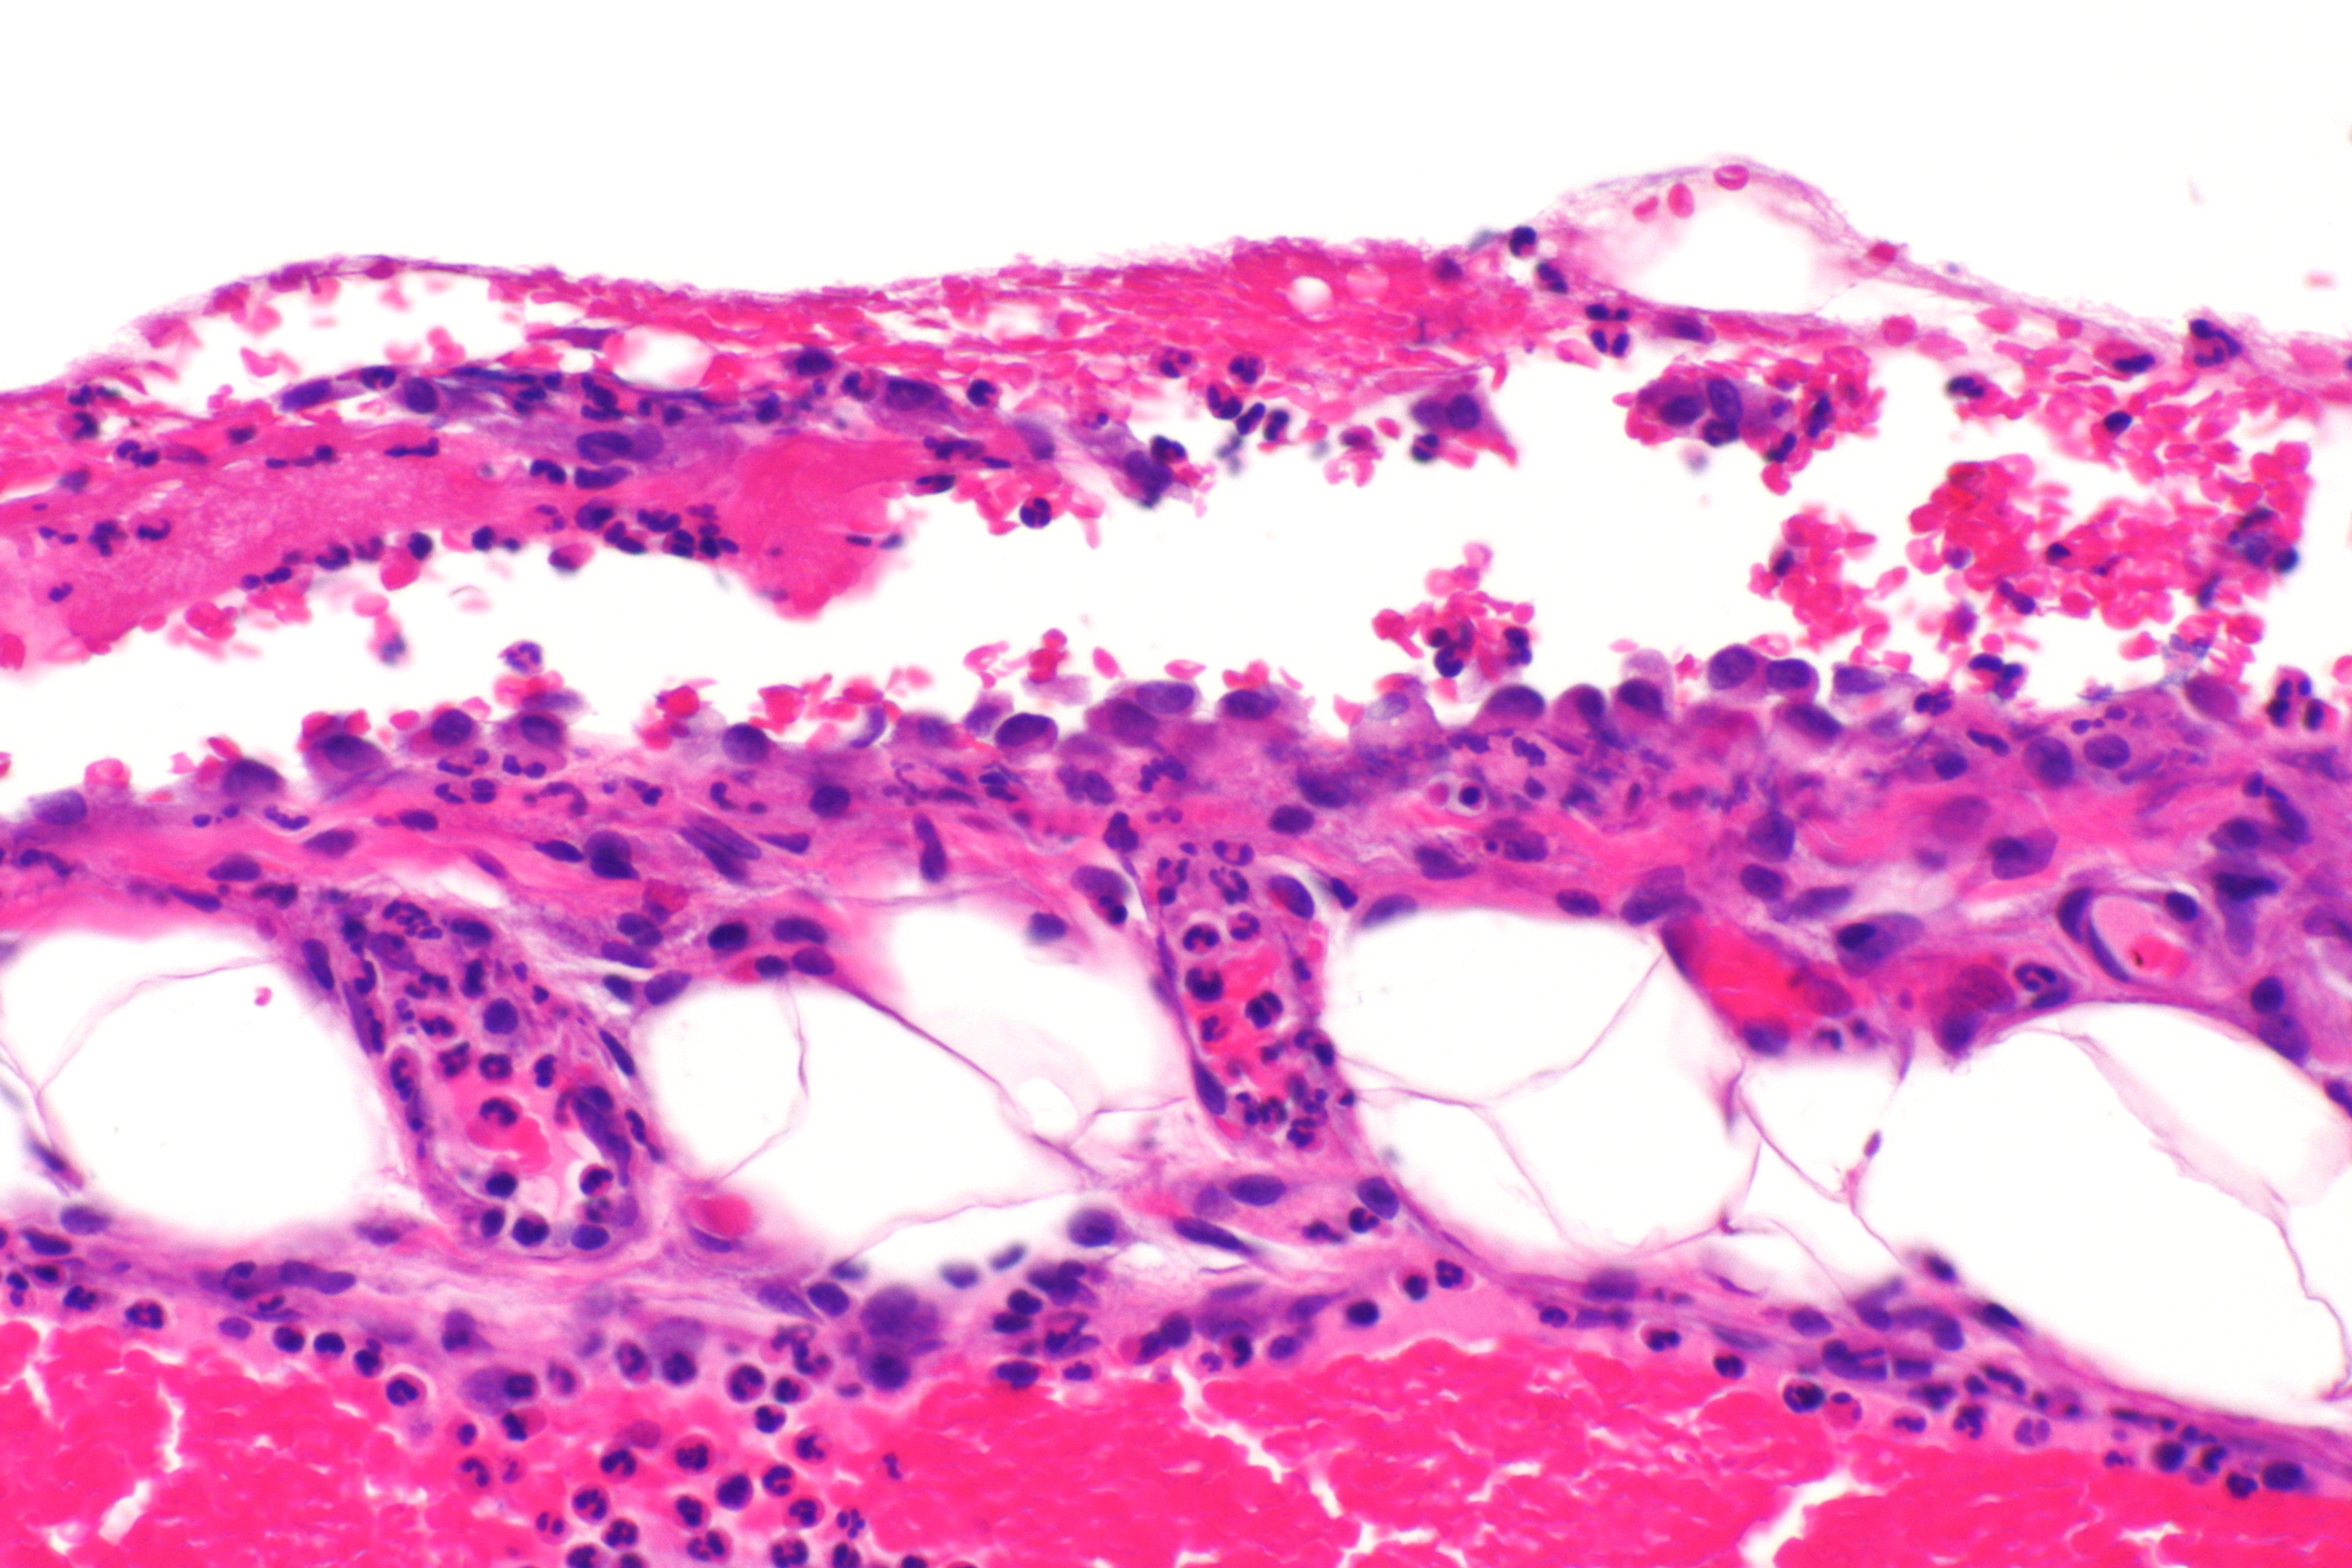

Årsaker til perikarditt deles inn i tre hovedgrupper: steril inflammasjon uten infeksjon, medikamentinduserte perikarditter og infeksjoner. Alle gruppene viser det samme inflammasjonsmønsteret i perikardet (7). Idiopatisk perikarditt, hvor man ikke finner en bakenforliggende årsak, er den hyppigste formen i den vestlige verden (1). En del av disse kan være viralt utløst, men diagnostikk for å differensiere mellom idiopatisk og viral årsak anbefales ikke rutinemessig (1). Perikarditt forekommer også etter myokardinfarkt, åpne og perkutane hjerteinngrep og traume (3). Metabolske sykdommer, tuberkulose, andre infeksjoner, kreft og revmatologisk sykdom er sjeldne årsaker i Norge. Perikarditt er dessuten en uvanlig primærmanifestasjon av disse sykdommene (7). Tuberkulose er fortsatt en hyppig årsak til perikarditt globalt og en viktig differensialdiagnose, da kurativ behandling er tilgjengelig.

På molekylært nivå er frigjøring av interleukin-1β og interleukin-18 sentralt i sykdomsutviklingen ved perikarditt (8). Dette skjer hovedsakelig fra inflammasomer i makrofager. Ved residiv skjer frigjøringen uavhengig av den opprinnelige årsaken, noe som er et typisk kjennetegn for autoinflammasjon (9). Tilstanden kalles derfor også for residiverende autoinflammatorisk perikarditt (9).